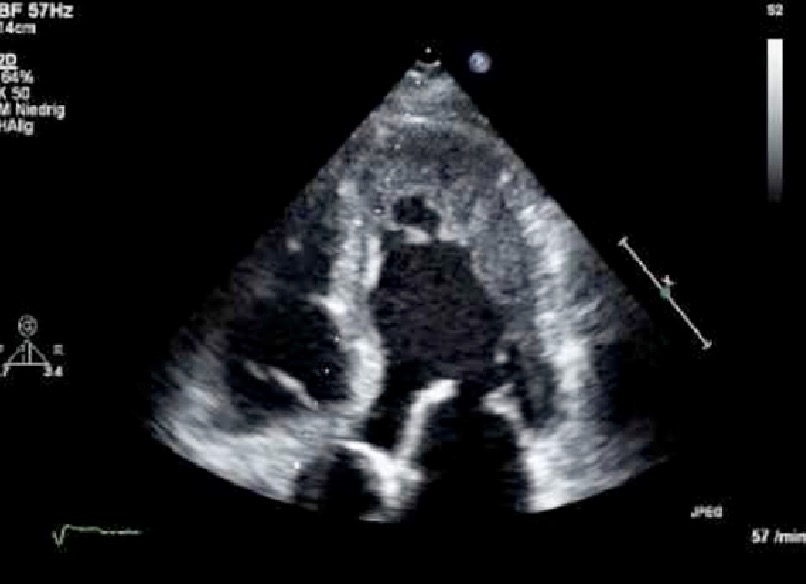

Arrhythmogenic RV Cardiomyopathy

What pathology does this ECHO look like?

Genetic form of cardiomyopathy that results in fibrofatty replacement of the RV wall

What do these ECHO findings align with…

rv dilation

Systolic dysfunction

RV trabeculation

Increased echogenicity of the moderator band